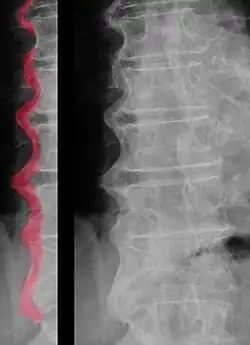

É principalmente caracterizada pela produção excessiva de tecido ósseo na zona das articulações, levando à calcificação das enteses e dos ligamentos.[2][3] Esta atividade de osteossíntese anormalmente elevada é particularmente observável nos ossos da coluna vertebral, por baixo do ligamento longitudinal anterior. No entanto, na região das vertebras torácicas, a formação anormal de osso é limitada ao lado direito destas.[2] Pensa-se que este fenómeno estará associado ao facto de a artéria aorta se localizar do lado esquerdo dos corpos vertebrais torácicos.[2][6]